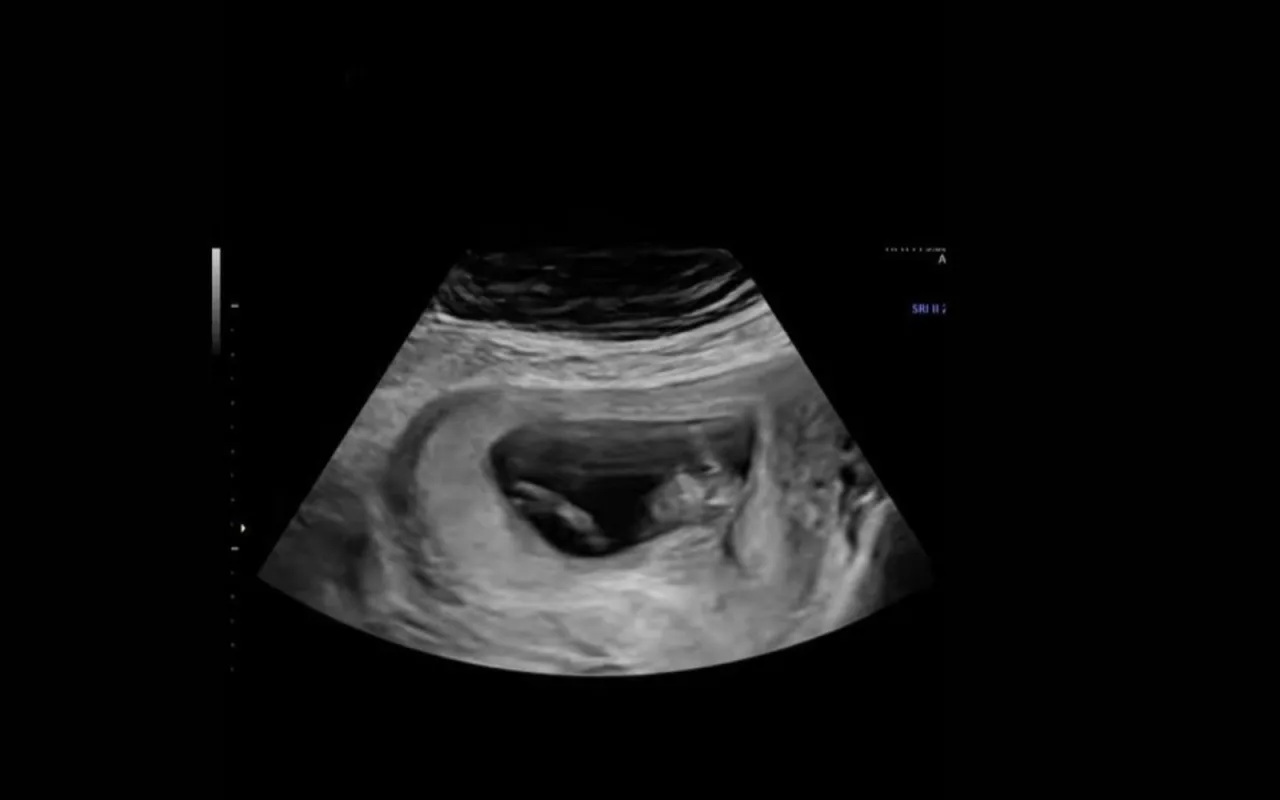

Το βίντεο έγινε viral με πάνω από 18 εκατ. views!Μία μέλλουσα μαμά δεν περίμενε, ότι θα γινόταν ο χαμός, όταν αποφάσισε να ανεβάσει ένα βίντεο από τον υπέρηχό της. Το clip στο TikTok δείχνει την αντίδραση του μωρού της, όταν εκείνη γελάει.

Το μωρό της, λοιπόν άρχισε, να πηδάει πάνω-κάτω μέσα στη μήτρα της. Η λεζάντα γράφει: «Σε περίπτωση που δεν γνωρίζεις, αυτό συμβαίνει στο μωρό σου, όταν γελάς. Κι εγώ το έμαθα με τον… δύσκολο τρόπο».

«Ήμουν 11 εβδομάδων έγκυος και ένιωθα σίγουρα πολύ αγχωμένη για το υπερηχογράφημα. Νομίζω πως όταν δεν βλέπεις το μωρό σου για μερικές εβδομάδες, είναι φυσιολογικό να νιώθεις μια μικρή ανησυχία», σημείωσε.

Κατά τη διάρκεια του ραντεβού με τον γιατρό, ο υπέρηχος κατέγραψε το μωρό να έχει λόξιγγα, κάτι που έκανε τη μαμά να ξεσπάσει σε γέλια.

Και τότε το σκηνικό έγινε ακόμη πιο αστείο. «Η πρώτη μου αντίδραση ήταν να κοιτάξω την οθόνη και να αρχίσω να γελάω ακόμη πιο δυνατά. Δεν είχα ξαναδεί κάτι αντίστοιχο πριν και πραγματικά είναι ό,τι πιο αστείο έχω δει μέχρι σήμερα. Ένιωθα λίγο άβολα, αλλά μόλις είδα τον υπέρηχο, ο γιατρός μου είπε ότι όλα ήταν άψογα», συνέχισε.